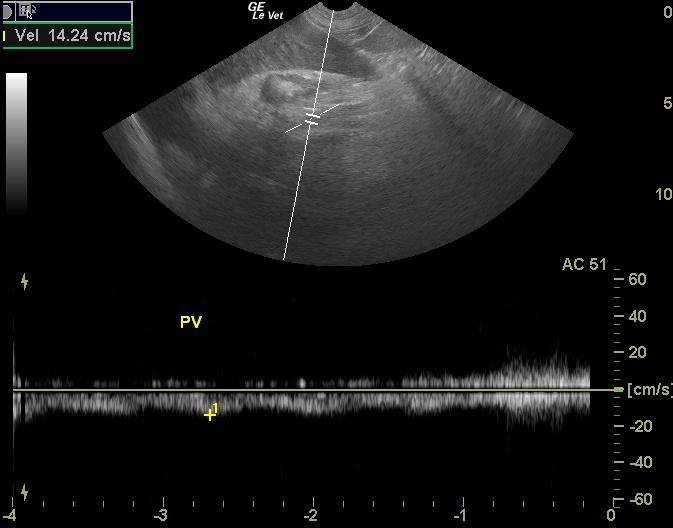

A 9-year-old FS Golden Retriever was presented for vomiting and anorexia. On physical examination pyrexia and tachycardia with ectopic beats were present. Abnormalities on CBC and blood chemistry were thrombocytopenia, monocytosis, moderately elevated ALT, elevated GGT, hyperbilirubinemia, mild hypernatremia, and marked hyperlipasemia. The patient was treated with I.V. fluids, Hetastarch, Baytril, and ampicillin. After 24 hours of therapy the patient`s temperature had normalized.